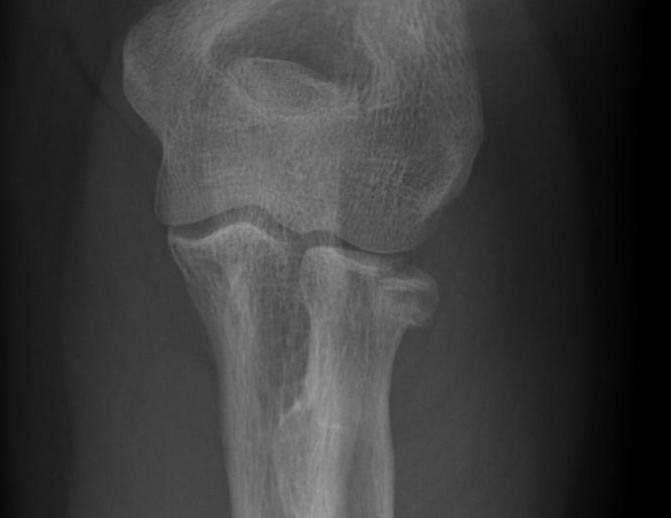

Hotchkiss modification of Mason Classification

Type 1: Undisplaced fracture / Intra-articular displacement < 2mm/ No mechanical limitation to forearm rotation

If in doubt, inject LA into radiocapitellar joint / soft spot and rotate elbow

Type I radial head fractures

Type 2: Displacement > 2mm / Motion mechanically limited / Reconstructable

Type 2 radial head fractures

Type 3: Severely comminuted fracture / Non reconstructable

Type 3 radial head fractures

Type 4: Radial head fracture with elbow dislocation

Type 4 radial head fractures